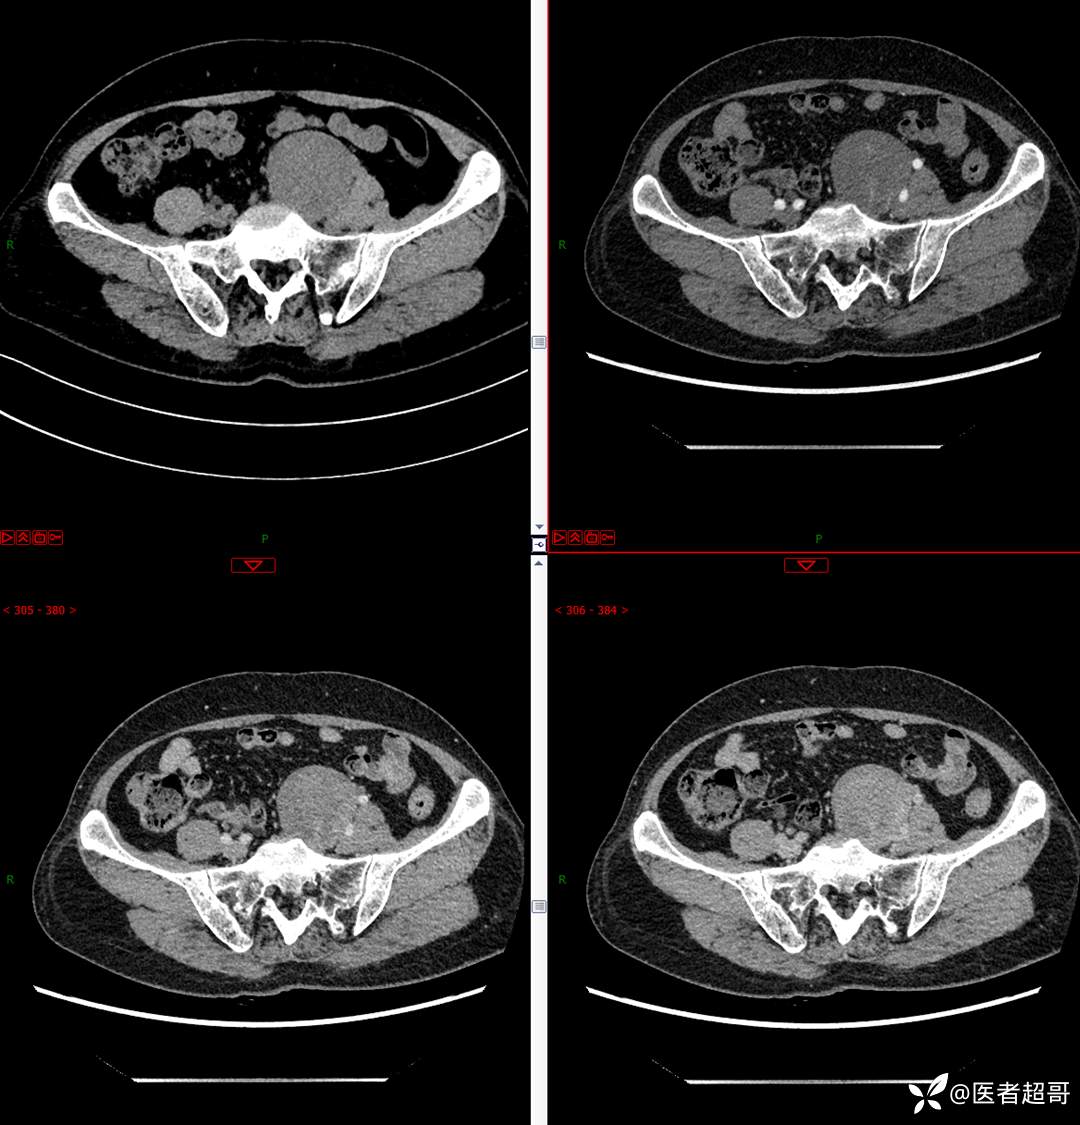

【影诊笔记559】查体发现右输尿管结石1周,发现腹膜后肿物,请分析,有病理!

•主 诉:查体发现右输尿管结石1周。

•现病史:患者1周前因小便不适来我院门诊行彩超检查提示右输尿管结石并右肾积水,伴腰疼,无血尿,无寒战,高热,患者求其进一步诊治,门诊以“右输尿管结石并右肾积水”收入院,患者自发病以来,神志清,精神可,饮食睡眠可,大便便秘,近期体重无明显增减。